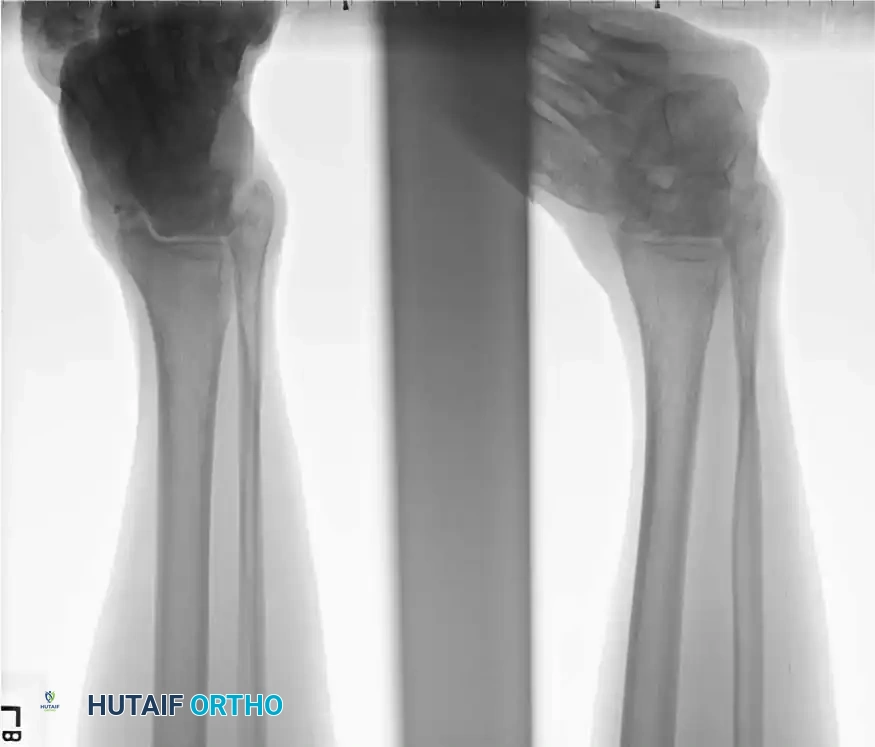

Standard trauma radiographs must include anteroposterior (AP), lateral, and mortise views of the ankle, alongside an AP, lateral, and oblique of the foot.

The Canale View:

Intraoperatively and postoperatively, the Canale view is indispensable for profiling the talar neck and assessing for varus malreduction. The foot is maximally plantarflexed and internally rotated 15 degrees, with the X-ray beam angled 75 degrees cephalad from the horizontal plane.

Radiographic positioning/Canale view

X-ray example of Canale View